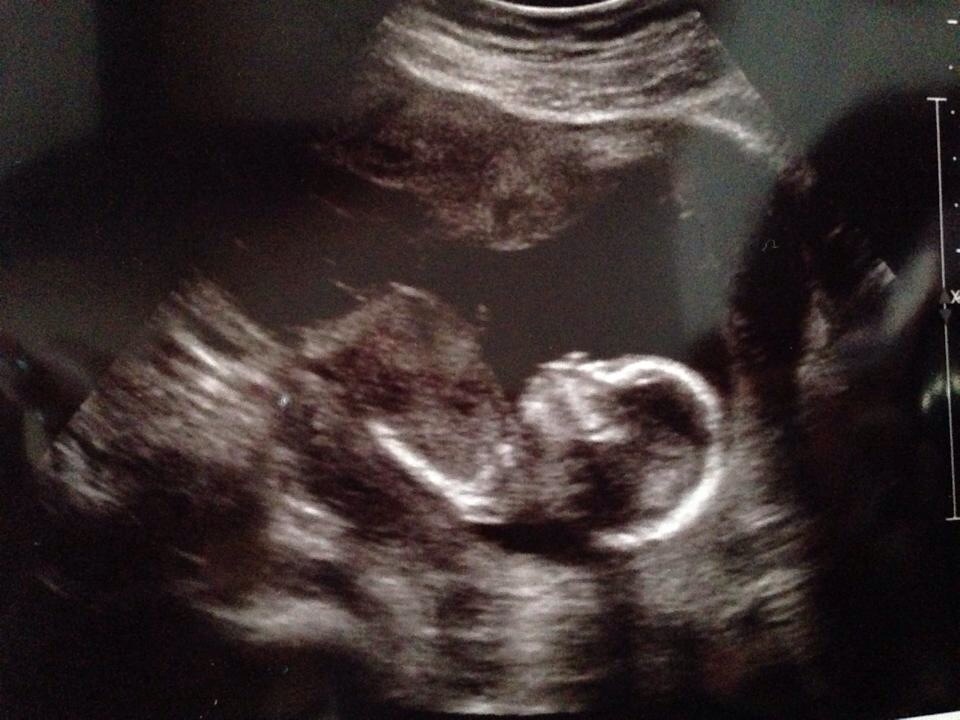

This is her baby boy... Looks the same to me so maybe another boy?